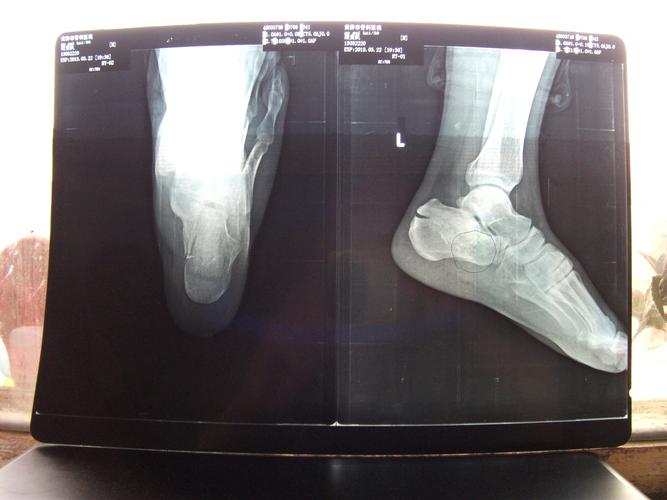

儿童跟骨正常x片,10岁小孩跟骨x光片

男42岁,跟骨骨折

跟骨骨折病例分享

跟骨骨折87天了专家们给看看!